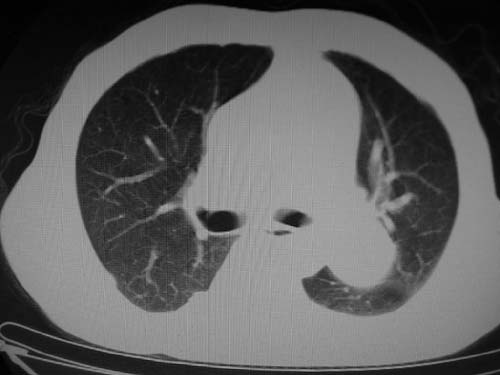

标题: CT17069:M80Y,请战友们看看像啥 [打印本页]

标题: CT17069:M80Y,请战友们看看像啥

男,80岁

肺a高压征[左肺a狭窄?];肺,胸膜tb

右肺上叶结核;左肺门占位?建议增强扫描.

左下肺静脉扩张,原因?建议cta

左肺动脉异常增粗,建议增强。

1)考虑肺动脉狭窄。2)右肺上叶继发性肺结核。3)右侧胸膜增厚、钙化,左侧胸膜反应。

肺动脉瘤。建议先行ct增强扫描

左肺动脉异常增粗,考虑肺动脉狭窄可能。

右肺上叶继发性肺结核。

右侧胸膜增厚、钙化,左侧胸膜反应。

左肺动脉异常增粗,建议ct增强,排除肺门肿瘤

右侧胸膜增厚、钙化,左侧胸膜反应

双肺陈旧性病变,左肺动脉高压.

1)考虑左肺动脉瘤可能性大,建议增强。2)右肺上叶继发性肺结核。3)右侧胸膜增厚、钙化,左侧胸膜反应。

肺动脉段突出,左右肺门不等大,左肺门明显增大,肺动脉干及左肺动脉明显增宽,考虑先天性肺动脉狭窄瓣膜狭窄型。

)考虑肺动脉扩张,右心室增大,主动脉弓段正常位弓后段明显变小(不会是动脉导客未闭吧,不知患者有何症状病史)0。2)右肺上叶继发性肺结核。3)右侧胸膜增厚、钙化,左侧胸膜反应。

右肺上叶尖段结核;左肺下叶占位?建议增强扫描。右侧胸膜增厚;右肺局限性肺气肿。

结合患者年龄,不除外左下肺扩张性动脉瘤,建议胸透是否有扩张性博动,以便确诊。

肺动脉高压,左肺动脉瘤样扩张。

肺a高压